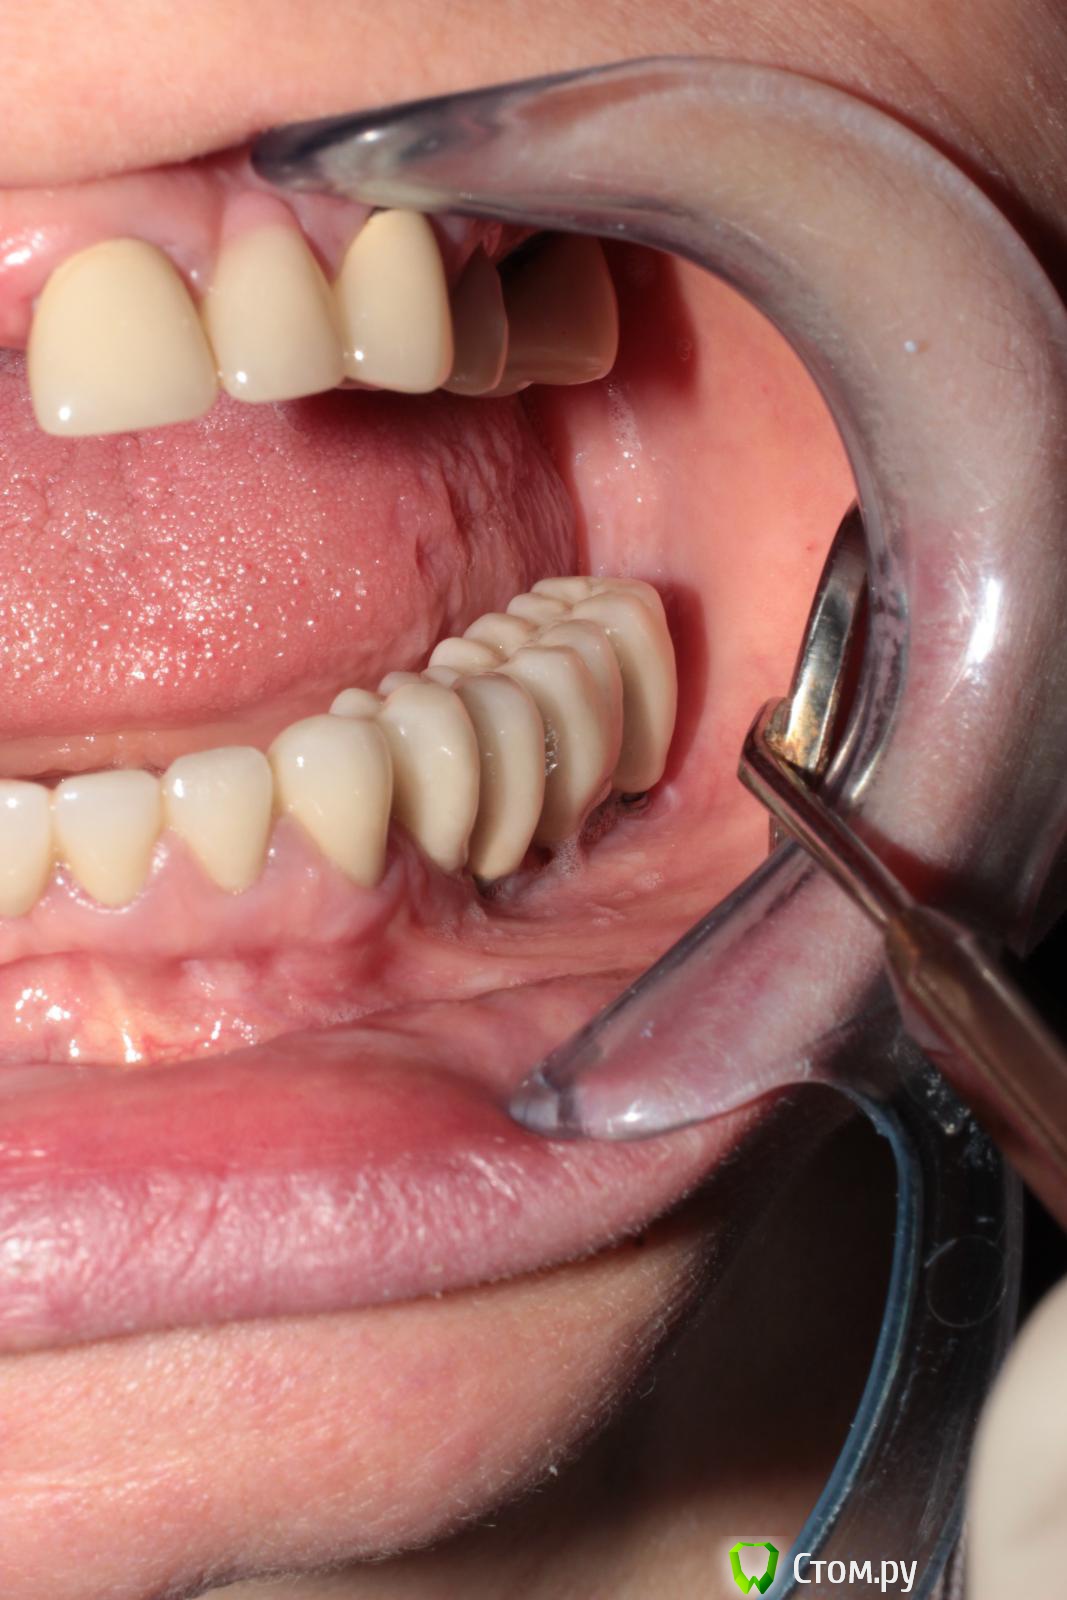

biv29 Опубликовано 30 апреля, 2014 Поделиться Опубликовано 30 апреля, 2014 (изменено) Уважаемые коллеги, прошу вашей помощи в составлении плана комплексной реабилитации пациентки.Пациентка 1962 г.р., 2 года назад были установлены имплантанты на н/ч, осуществлено протезирование (работал другой стоматолог-ортопед). Имеется вертикальная резорбция кости н/ч, рецессия десны, оголение имплантантов.На в/ч сохранены 17, 21, 23, 24, 27. Установлен ЧСПП. 21-23 МК-мостовидный протез (коронка 23 не доходит до десневого края). 24 - временная пластмассовая коронка.Имеется снижение высоты прикуса.- Я склоняюсь к следующему варианту работы:удаление 17, 21, 23, 24, 27; проведение синус-лифтингов с двух сторон, аугментация, установка имплантантов; временное протезирование на время реабилитации после операции, временное протезирование на пластмассовых коронках, постоянное протезирование МК.1. При этом плане возникает вопрос о временном протезировании сразу после хирургического вмешательства. Имплантолог против установки ПСПП на в/ч. Как поступить в этом случае? Использовать ли стабилизацию ПСПП и его фиксацию на мини-имплантантах? Достаточно ли будет мягкой подкладки на внутренней поверхности ПСПП?2. Считаете ли целесообразным осуществить протезирование сначала на в/ч без переделки орт. конструкций на н/ч? 3. 21, 23, 24 - стоит удалять или есть вероятность, что еще послужат? 4. Какой план протезирования вы бы предложили в данной клинической ситуации? Заранее спасибо за возможные ответы. Изменено 30 апреля, 2014 пользователем biv29 Ссылка на комментарий